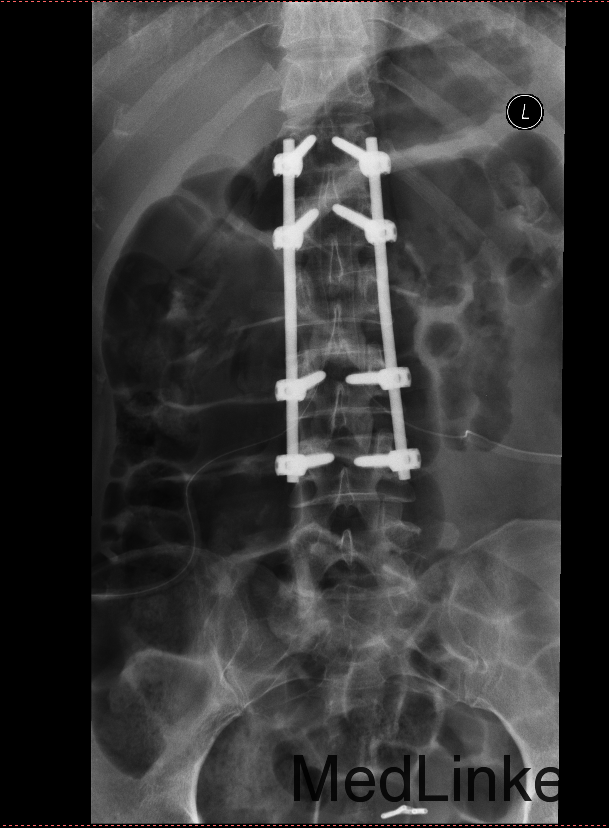

主诉:摔伤后腰痛伴活动受限5天 现病史:患者自述于2015-4-21日下午5点左右摔倒,臀部先着地。后自觉腰部疼痛伴活动受限,位置固定,无放散性疼痛,当日就诊于灯塔市中心医院,行DR及CT检查示腰椎L2压缩骨折,现患者为求进一步诊治来我院就诊,急诊以“腰椎压缩骨折”为诊断收住院治疗。病来无发热,无头痛及头晕,无恶心,呕吐,无胸痛及呼吸困难,无腹胀及腹痛,饮食,睡眠良好,大小便未及异常。

诊断 : 腰2椎体压缩性骨折; 患者入院后完善检查,完善肌电图等检查,查无手术禁忌症后行腰椎压缩骨折切开复位椎板减压椎管扩大椎弓根钉内固定术。术后患者生命体征平稳,无发烧发热,局部切口患者示良好,患者三天后拔除引流管后,自动退院